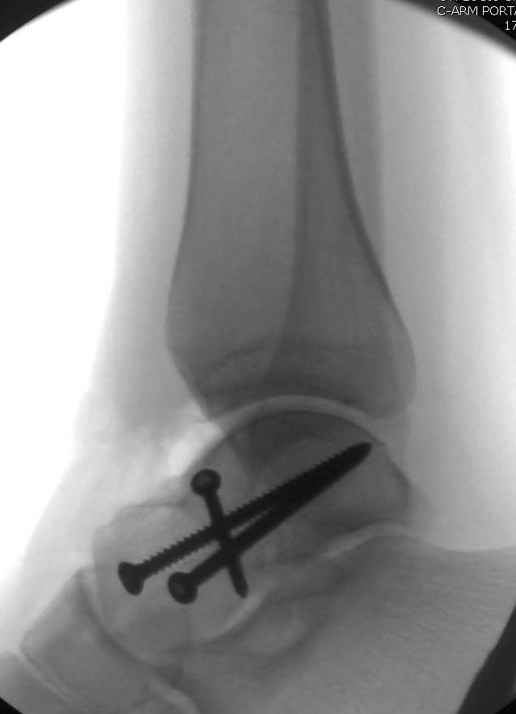

Вдогонку по поводу перелома таранной кости, больная 81, не страдает диабетом, перелом закрытый, в первый же день поступления ограничились временным наружным фиксатором (как на снимке).

Планировалась открытая фиксация после спадения отека, но больная пожелала лечиться по месту жительству в другом штате..

Из-за отека на стопе тактика лечения у всех была

одинаковая: временная наружная фиксация до спадения отека, при изолированных переломах они выписывались домой и через дней 7 госпитализировались на оперативное лечение.

Примеры на снимке...